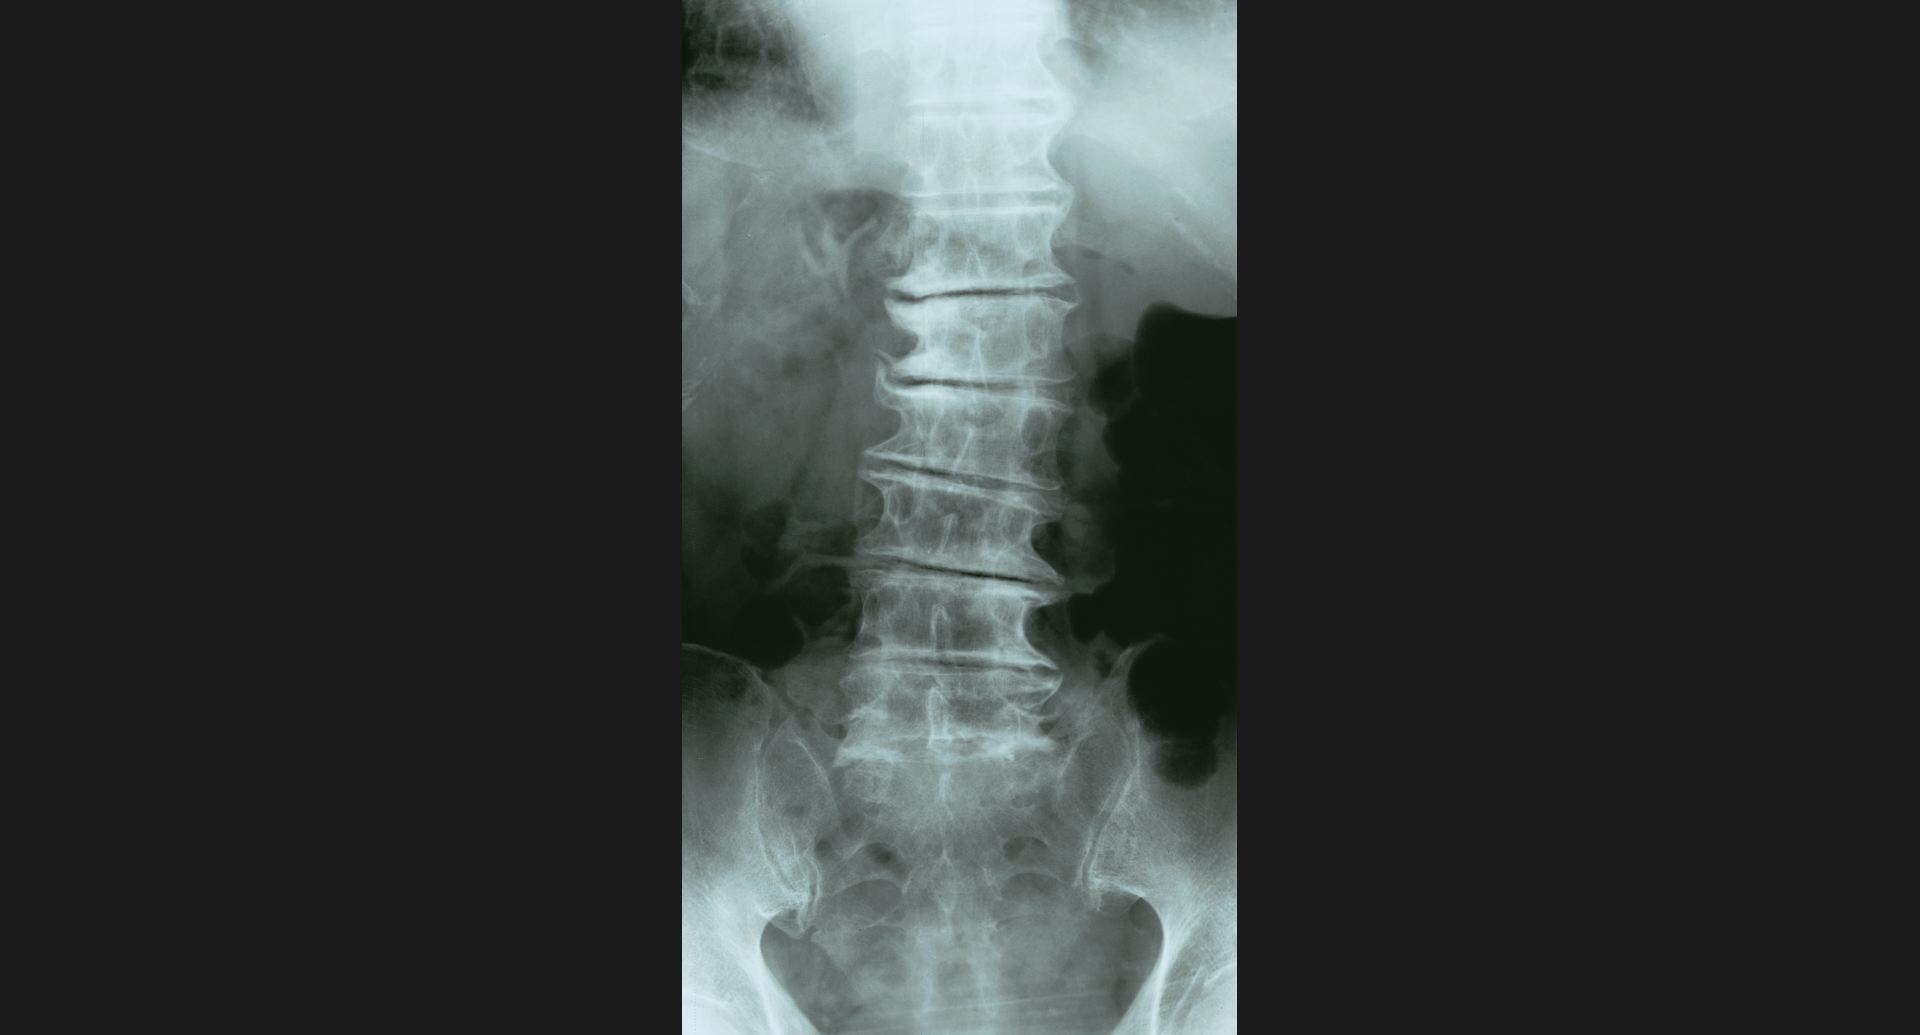

:Phantom discdisc内の透亮像。spur。

fig.15(55KB)